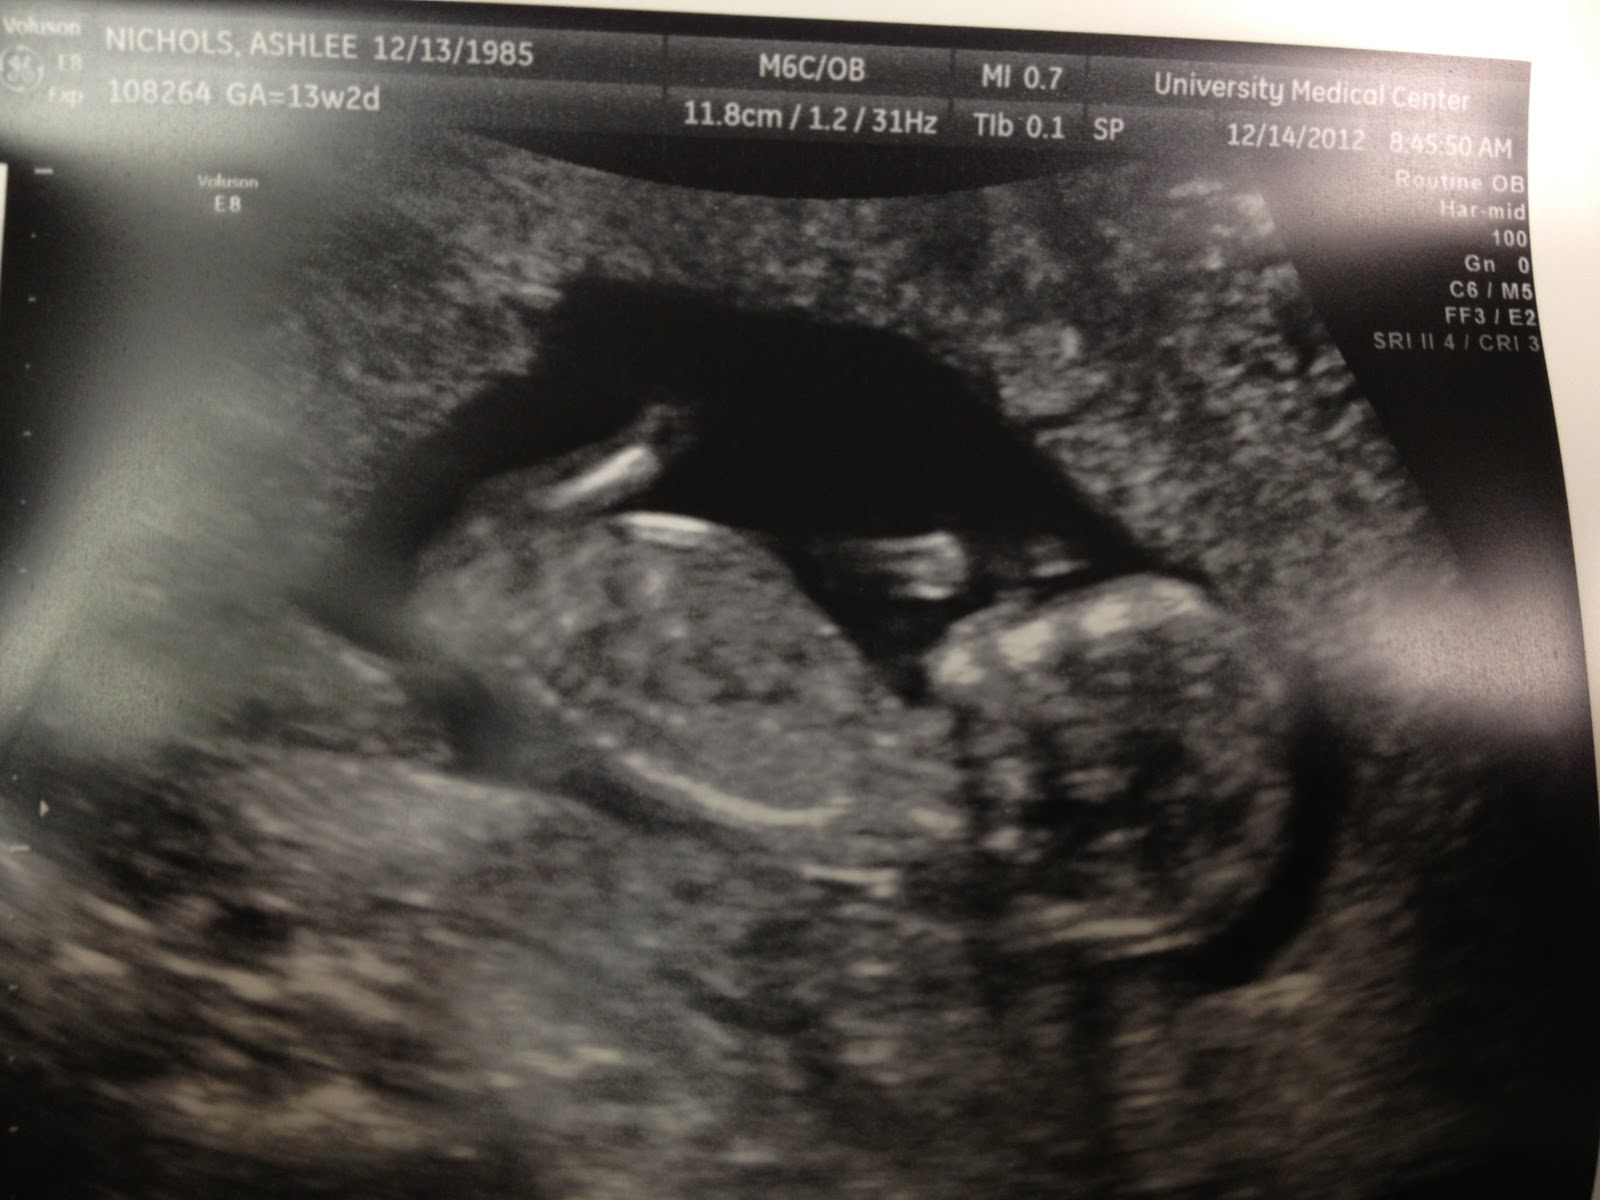

- Best Moment of the Week: Getting to see Baby!!! We had the NT Scan and baby was standing on its head the whole time so they didn’t even get to do the testing. But, we got to see baby and he/she is so healthy! BPM was 147 and growth is right on track. He/she even waved for us! Sweet little thing! I had a good birthday, too! 🙂 27 is looking pretty good!

Here are some pics from our 13 week ultrasound!

Sweet baby waving “hi” to us! Five sweet little fingers!